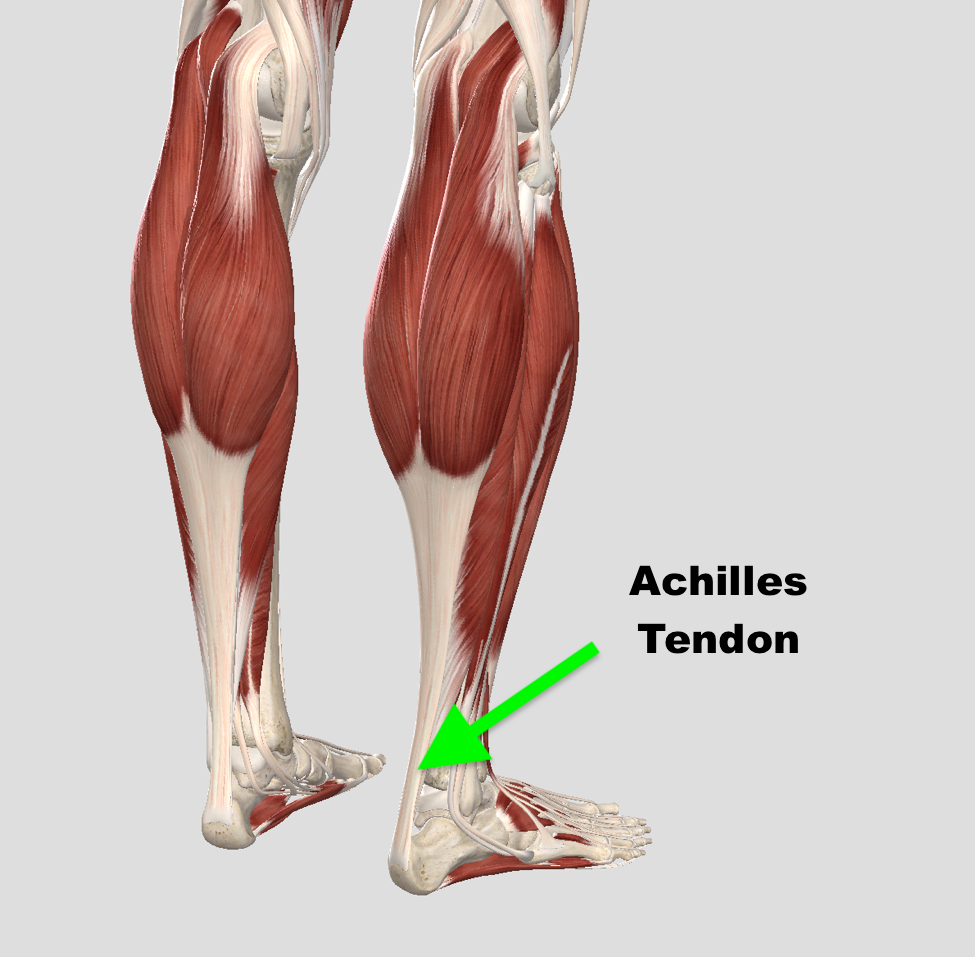

pictures of achilles tendon

Achilles Tendon – Squat University

Achilles Tendon – NJSM

Achilles Tendon Diagram – 1000+ images about medical anatomy on …